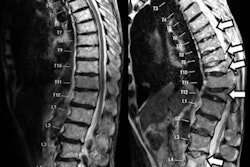

The spine is the most frequent location of skeletal metastases. Therefore, the CAD algorithm is focused on thoracolumbar vertebral bodies, which are the most common spinal metastases, Summers said.

The algorithm was tested on a database that included PET/CT images from 53 patients (mean age, 53 years) with lytic, sclerotic, or mixed lesion types. Section thickness was 3.75 mm for the clinically obtained images, representing 225 lytic, 139 sclerotic, and 92 mixed lesions. Exclusion criteria ruled out patients with spinal hardware, vertebroplasty cement, or significant artifacts.

CAD generated 32 false-positive detections among 18 control cases, mostly due to the presence of bone islands. Spinal lesions ranged in size from 4 mm to 37 mm and were most common in T9 to T12. A few false-negative detections occurred in small lesions.